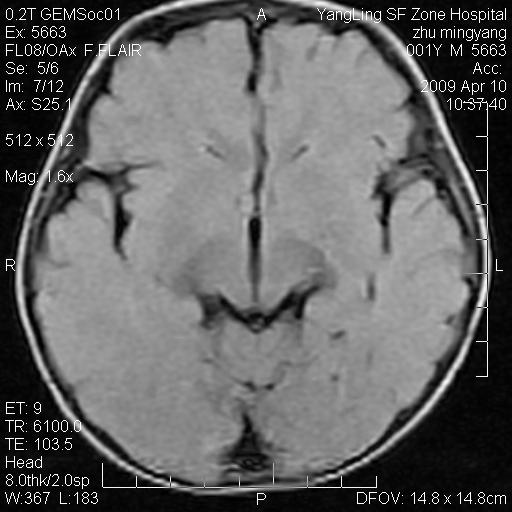

患者:1岁半,两天前外伤收住我院,ct检查小脑占位

考虑星形细胞瘤,建议增强

髓母细胞瘤或血管母细胞瘤,增强后可以鉴别;影像资料见 <。鱼博浪老师的《中枢神经系统ct与mr鉴别诊断》 小脑部肿瘤章节。

髓母细胞瘤或血管母细胞瘤!支持!

支持考虑髓母细胞瘤

考虑----髓母细胞瘤可能性大

考虑髓母细胞瘤或室管膜瘤。

支持髓母细胞瘤。

考虑髓母细胞瘤。

考虑髓母细胞瘤或星形细胞瘤

考虑髓母细胞瘤.

考虑髓母细胞瘤可能性大。

小脑肿瘤.考虑髓母细胞瘤可能.

就病灶部位及临床资料首先考虑髓母.